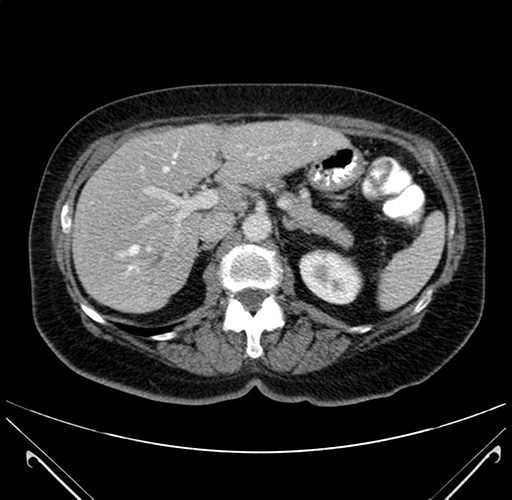

Pre-Chemo: Axial Venous

Axial Venous